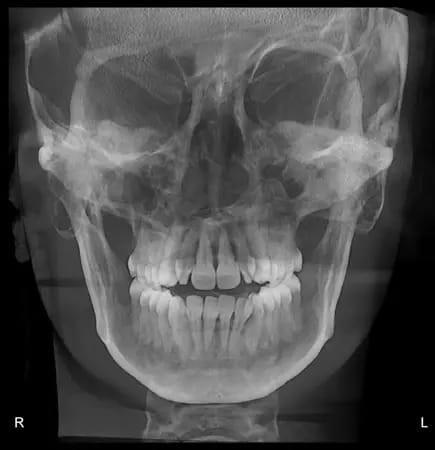

Панорамная рентгенограмма показала предварительное удаление всех третьих моляров, локальную резорбцию корней нескольких зубов, в целом хорошее состояние пародонта и атипичную морфологию мыщелков, свидетельствующую о ремоделировании височно-нижнечелюстного сустава (ВНЧС) или дегенеративных изменениях (фото 19). Цефалометрическая рентгенограмма и трассировка выявили мезобрахиально-лицевой тип скелета и тенденцию к формированию скелета II класса (фото 20).

Фото 19: Дооперационная панорамная рентгенограмма.